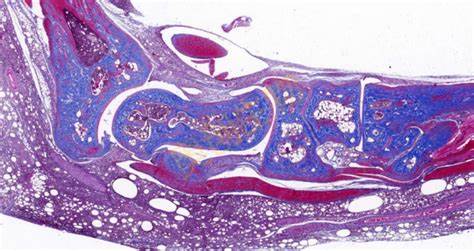

2. 弹力纤维染色

- 原理:弹力纤维的主要成分是弹性蛋白,它在一些组织(如血管壁、皮肤等)中发挥重要作用。常用的染色方法有维多利亚蓝染色法和地衣红染色法。以维多利亚蓝染色法为例,维多利亚蓝是一种碱性染料,它能与弹力纤维中的酸性基团结合,使弹力纤维染成蓝色,从而清晰地显示出弹力纤维在组织中的分布和形态。

3. 弹力纤维染色

- 弹力纤维染成蓝色(以维多利亚蓝染色为例)。在血管壁中,弹力纤维呈环形或螺旋形分布,能够观察到动脉壁的弹力层结构。在皮肤组织中,弹力纤维存在于真皮层,与皮肤的弹性有关。通过观察弹力纤维的染色,可以了解血管和皮肤等组织的病变情况。